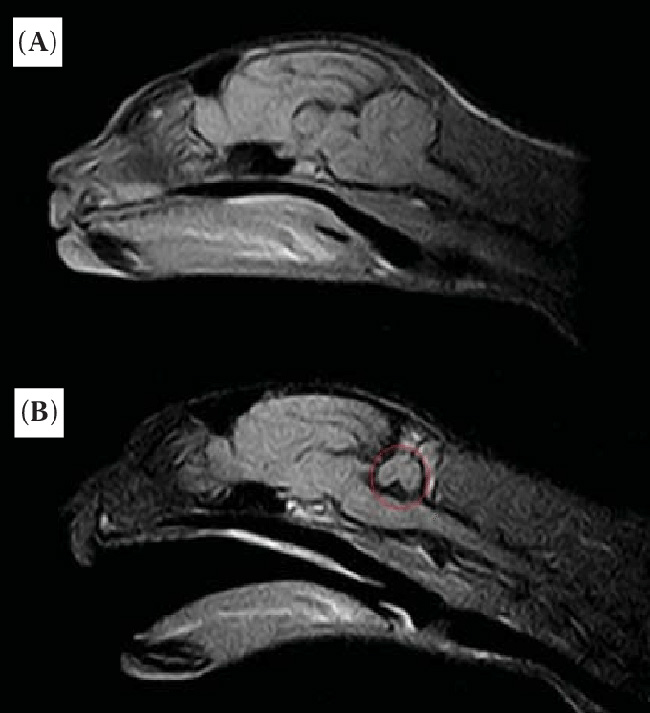

Risonanza magnetica della testa di un gatto (Researchgate)